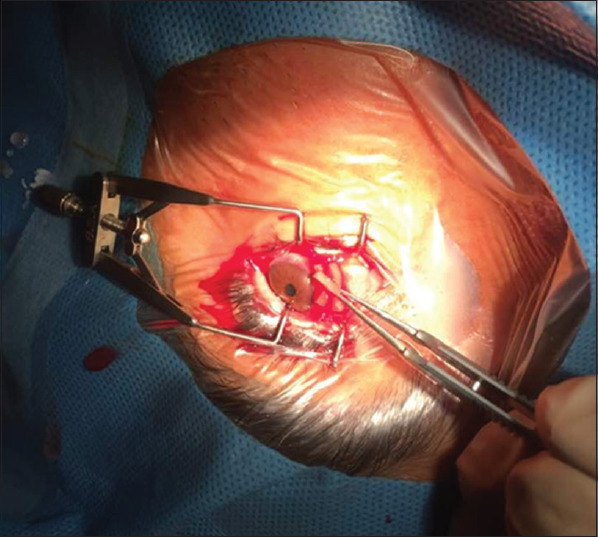

Results: MMC has been widely utilized in ophthalmic surgery due to its effects on the wound-healing process. The main current applications include pterygium surgery, glaucoma filtering surgery, surgical treatment of ocular surface tumors, eye alignment surgeries, dacryocystorhinostomy, and corneal refractive surgery.

Abstract Image